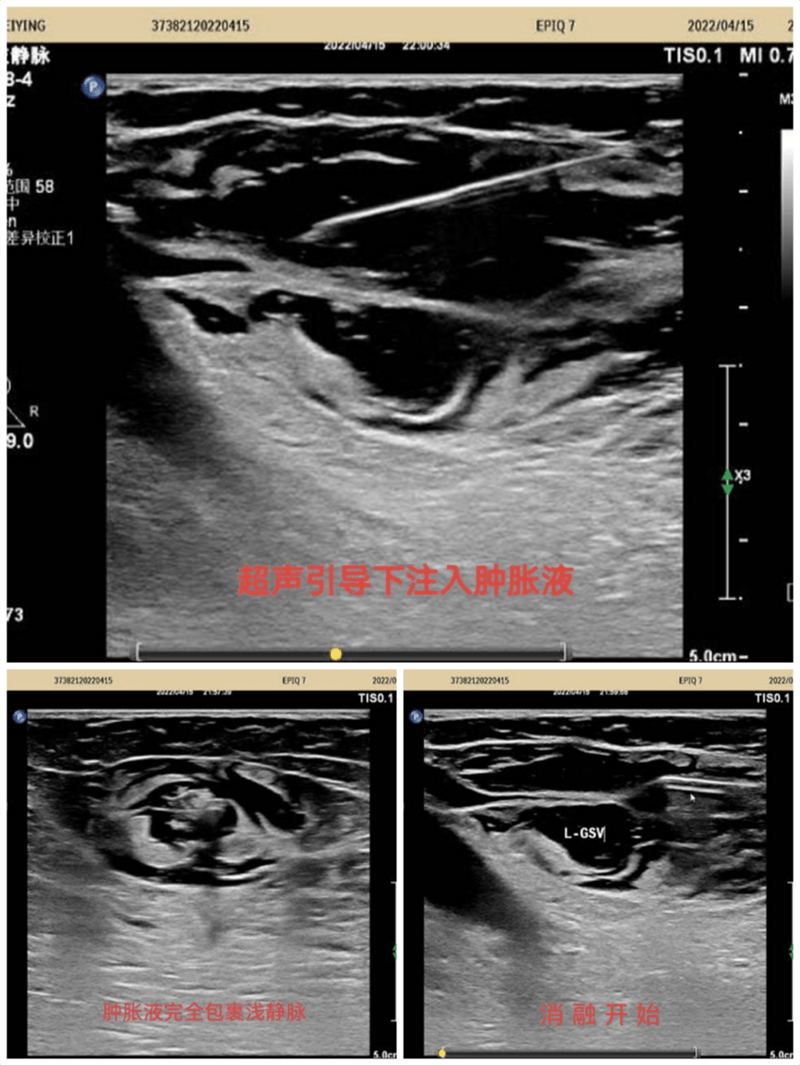

超聲引導下標記大隱靜脈及曲張靜脈部位走行,體表投影部位標記,在彩色多普勒超聲靜脈模式引導下實時監(jiān)測,確定穿刺點,局麻下穿刺進針,確定穿刺成功后置入導絲,拔除穿刺針并沿導絲置入7F鞘管,拔出導絲,沿鞘管將消融電極置入要消融的大隱靜脈主干內(nèi),注入腫脹麻醉液,確認大隱脈閉合,開啟移動射頻消融導管,消融完畢后拔除鞘管及射頻導管再次超聲探查隱股靜脈交界處,確定無血栓形成。